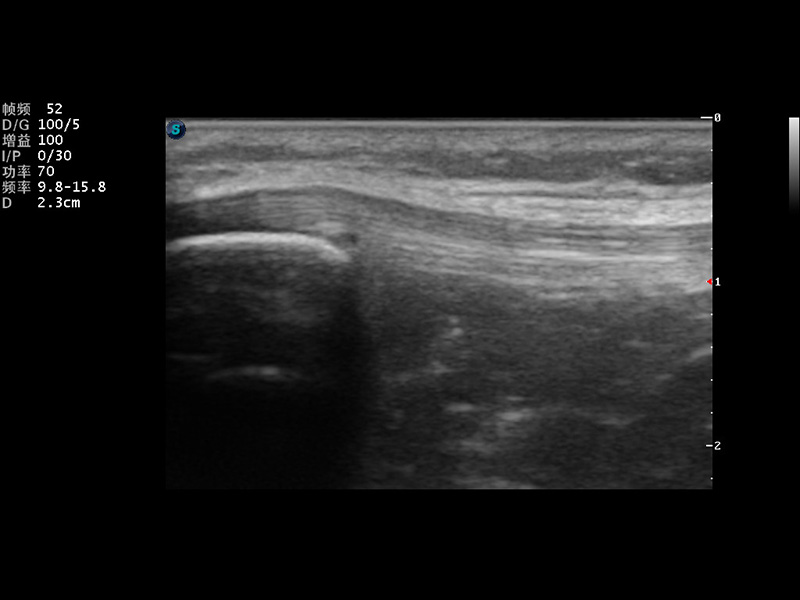

S9便携式彩色多普勒超声诊断仪是公海贵宾会员检测中心医疗研发的高端便携彩超设备,外观设计新颖、产品性能卓越。S9在便携超声领域采用了突破传统的触摸屏交互设计,并以先进的软件硬件技术和设计理念,为您带来清晰的图像质量、稳定的工作性能和便捷的操作体验。

成像技术

μ-Scan微米成像